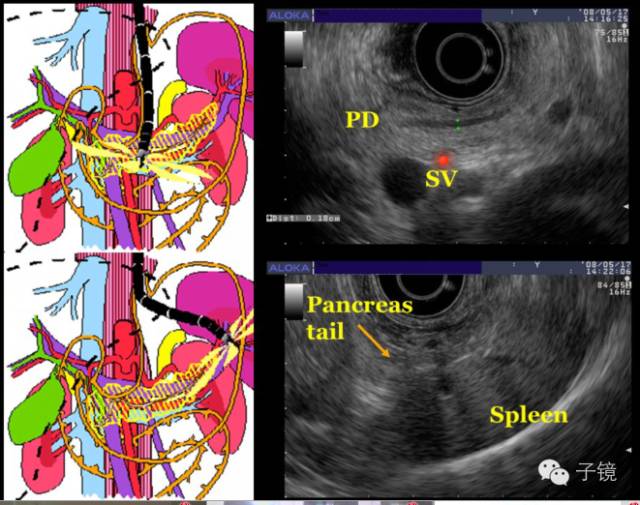

EUS是诊断胰腺疾病非常重要的工具。有环扫EUS和扇扫的EUS。

李玉棠教授答:平常工作中,自己一般是先使用超声内镜的内视镜功能先检查上消化道,然后退镜的同时进行胰胰、胃、食道,甚至纵膈、甲状腺等全超声检查。

11、祝喜萍教授问:全内镜+全超声内镜检查哪些部位需要重点观察?

李玉棠教授答:扫描时先把水囊打起来,在贲门部看清楚胃跟食道有无炎症,然后在胃体压住大弯看贲门部。在十二指肠球部有一些困难,可能需要在胃窦部看十二指肠,必要时需用换胃镜补充检查。